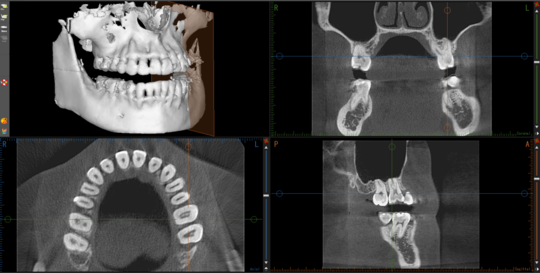

③CT

立体のレントゲン

CTは3次元(3D:立体)のレントゲンです

もともとは矯正歯科で使用するものではありませんでした

当院でもインプラント治療やそのほかの手術、根の治療などに役立ててきました

それが2023年より

インビザラインシステムに組み込むことができるようになりました

それまで多少の参考程度しか考慮することができなかった

歯根やそれを支える骨(上顎骨と下顎骨)

の状態も完璧に把握することが可能になりました

特に

骨の形態は基本的には変えられません

どんな矯正方法であっても

歯は骨があるところにしか並べることができないのです

骨がないところに配置するような力をかけてしまうと

歯は骨から離脱することになります

すなわち矯正をすることで抜歯状態に近くなるということです

CTを組み合わせると

歯を動かせる範囲が完璧にわかります

安全性と確実性が大きく向上した、と言えます

私たちにおいても、CTのあるなしでは

計画を立てる際の安心感

が全く違います

現状、CTを矯正に組み込むことができるのは

デジタル計画を立てることができるシステムのごく一部

となっています

ワイヤー矯正はアナログなものですので

マウスピース矯正システムのごく一部となります